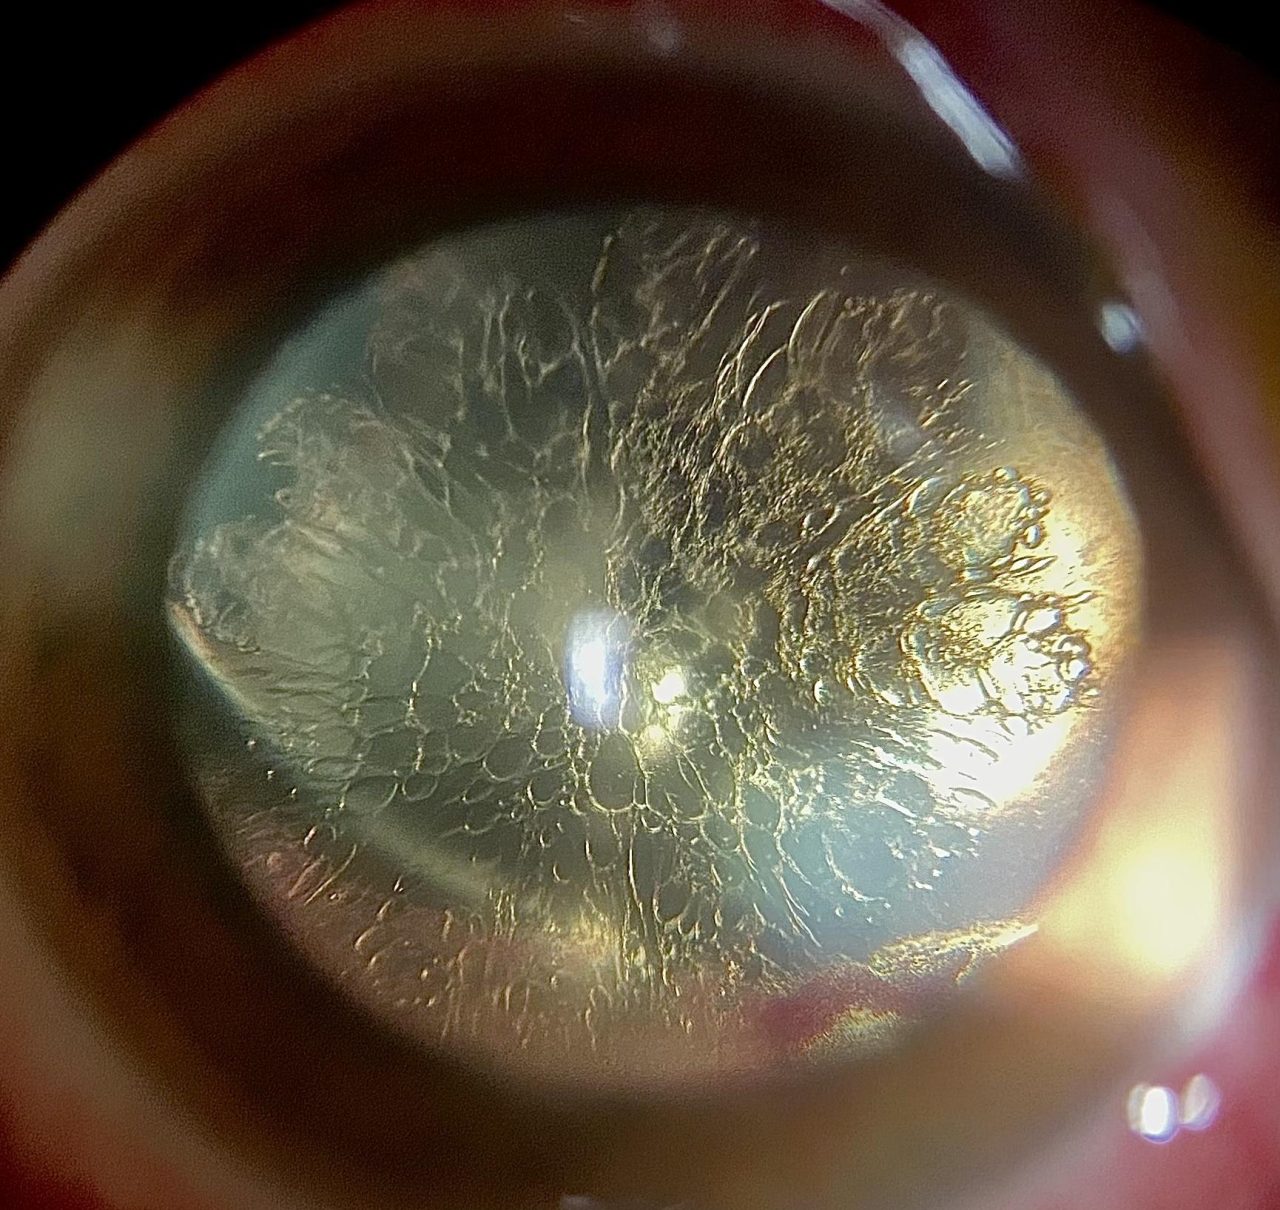

Kαταρράκτης λέγεται η θόλωση ή η αδιαφάνεια του φακού στο εσωτερικό του ματιού.

Μέσα στο μάτι πίσω από το χρωματιστό μέρος (ίριδα) με μια μαύρη οπή στη μέση (η κόρη), είναι ο φακός του ματιού. Σε ένα κανονικό μάτι αυτός ο φακός είναι διαυγής και βοηθά στην εστίαση των ακτίνων φωτός στο πίσω μέρος του ματιού (τον αμφιβληστροειδή), ο οποίος στέλνει μηνύματα στον εγκέφαλο που μας επιτρέπουν να βλέπουμε. Όταν αναπτύσσεται καταρράκτης ο φακός γίνεται θολός και εμποδίζει τις ακτίνες φωτός να περάσουν με αποτέλεσμα να μειώνεται η όραση και να γίνεται θαμπή και θολή «σαν να βλέπεις μέσα από ένα βρώμικο τζάμι».

Ο καταρράκτης συνήθως σχηματίζεται αργά και οι περισσότεροι άνθρωποι βιώνουν μια σταδιακή θόλωση της όρασης η οποία εμφανίζεται συνήθως μετά τα 60 (γεροντικός καταρράκτης). Υπάρχουν όμως και άλλοι λόγοι για τους οποίους μπορεί να εμφανίσετε καταρράκτη και περιλαμβάνουν: